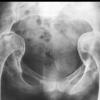

(三)X线检查:肠道钡剂检查有助于病损范围与性质的确定。但征象无特异性。钡剂灌肠示结肠粘膜呈细小的锯齿样边缘,皱壁不规则,肠壁僵硬或痉挛。有时可见肠段狭窄、溃疡和瘘管形成。少数溃疡边缘的粘膜可隆起,其X线征酷似癌肿,其鉴别点是病变段与正常肠段间逐渐移行而无截然的分界限,与癌肿不同。乙状结肠位置较低并折叠成角。应从不同角度摄片对鉴别病变性质有重要意义。

钡剂检查小肠,可见病变常以回肠末端为主。充钡时,可见管腔不规则狭窄,并因粘连而牵拉成角,形成芒刺样阴影,肠壁增厚、肠曲间距增宽。也可见肠腔结节样充盈缺损,与炎性肠病相似。排空时小肠正常羽毛状粘膜纹消失。近年来用肠系膜血管造影有助于发现小血管病变。对于放射性肠炎的早期诊断与鉴别诊断有一定意义。